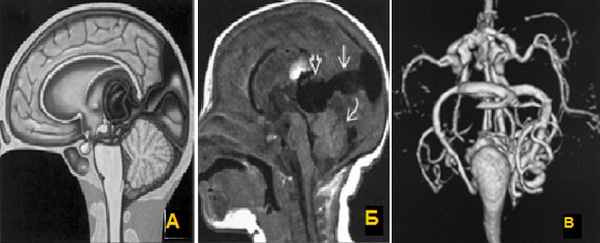

2. Мальформация большой вены мозга (вены Галена).

Центрально расположенная АВМ, дренирующаяся в вену Галена, с формированием ее варикозного расширения. У новорожденных могут возникать явления сердечной недостаточности за счет большого объема шунтового кровотока.

а) Мальформация (варикозное расширение) вены Галена, схема.

б)Т1-sag определяется расширенная вена Галена (открытая стрелка), дренирующаяся (стрелка) в сагиттальный синус;

в) МР-объемная реконструкция.